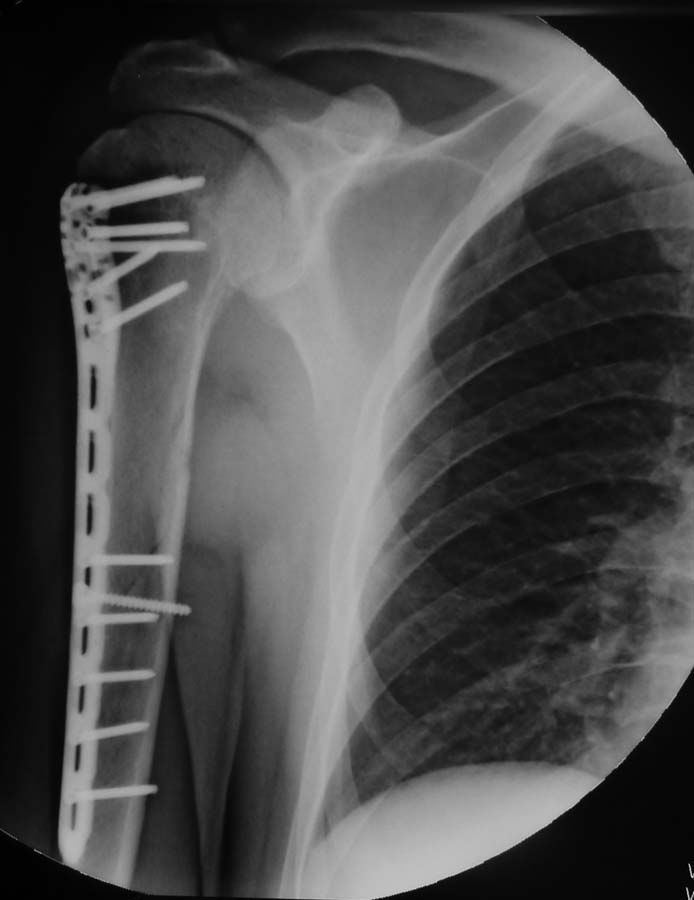

[Ortho] Сочетание перелома диафиза и головки плеча - рентгеноконтроль

Уважаемые коллеги. В дискуссии по сообщению от 28 июля одним из участников было высказано

сомнение в правильности выбора длины пластины, в ответ на которое я пообещал представить

контрольные рентгенограммы.

Снимки через 41 день после операции: консолидация по типу первичной.